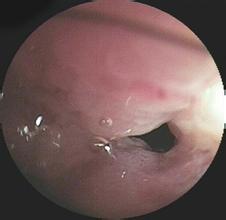

急性出血性壞死性小腸炎癥狀

1.病史 起病急,發(fā)病前多有不潔飲食史。受冷、勞累,腸道蛔蟲(chóng)感染及營(yíng)養(yǎng)不良為誘發(fā)因素。

2.腹痛 起病急驟,突然出現(xiàn)腹痛,也??蔀樽钕劝Y狀,多在臍周。病初常表現(xiàn)為逐漸加劇的臍周或中上腹陣發(fā)性絞痛,其后逐漸轉(zhuǎn)為全腹持續(xù)性痛并有陣發(fā)性加劇。

3.腹瀉便血 腹痛發(fā)生后即可有腹瀉。糞便初為糊狀而帶糞質(zhì),其后漸為黃水樣,繼之即呈白水狀或呈赤豆湯和果醬樣,甚至可呈鮮血狀或暗紅色血塊,糞便少而且惡臭。無(wú)里急后重。出血量多少不定,輕者可僅有腹瀉,或僅為糞便隱血陽(yáng)性而無(wú)便血;嚴(yán)重者一天出血量可達(dá)數(shù)百毫升。腹瀉和便血時(shí)間短者僅1~2天,長(zhǎng)者可達(dá)一月余,且可呈間歇發(fā)作,或反復(fù)多次發(fā)作。腹瀉嚴(yán)重者可出現(xiàn)脫水和代謝性酸中毒等。

4.惡心嘔吐 常與腹痛、腹瀉同時(shí)發(fā)生。嘔吐物可為黃水樣,咖啡樣或血水樣,亦可嘔吐膽汁。

5.全身癥狀 起病后即可出現(xiàn)全身不適,軟弱和發(fā)熱等全身癥狀。發(fā)熱一般在38~39℃,少數(shù)可達(dá)41~42℃,但發(fā)熱多于4~7天漸退,而持續(xù)2周以上者少見(jiàn)。

6.腹部體征 相對(duì)較少。有時(shí)可有腹部飽脹、見(jiàn)到腸型。臍周和上腹部可有明顯壓痛。早期腸鳴音可亢進(jìn),而后可減弱或消失。